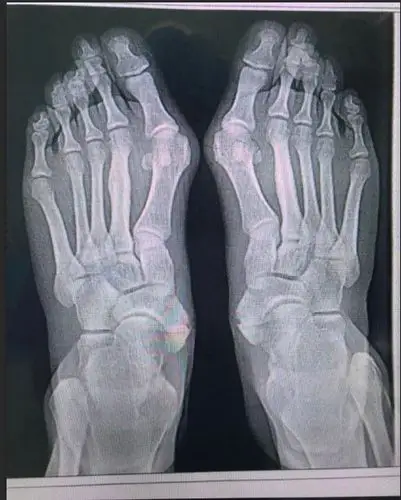

重度大脚骨

18岁女孩和妈妈都是大脚骨,是遗传吗,怎么治?骨科老牛来支招!

走路疼痛,不敢穿凉鞋?这里有治疗大脚骨的好方法

拇外翻大脚骨手术矫治术